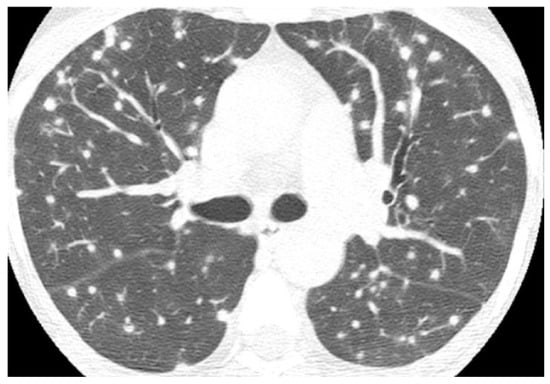

2.1. Lung Nodule or Mass